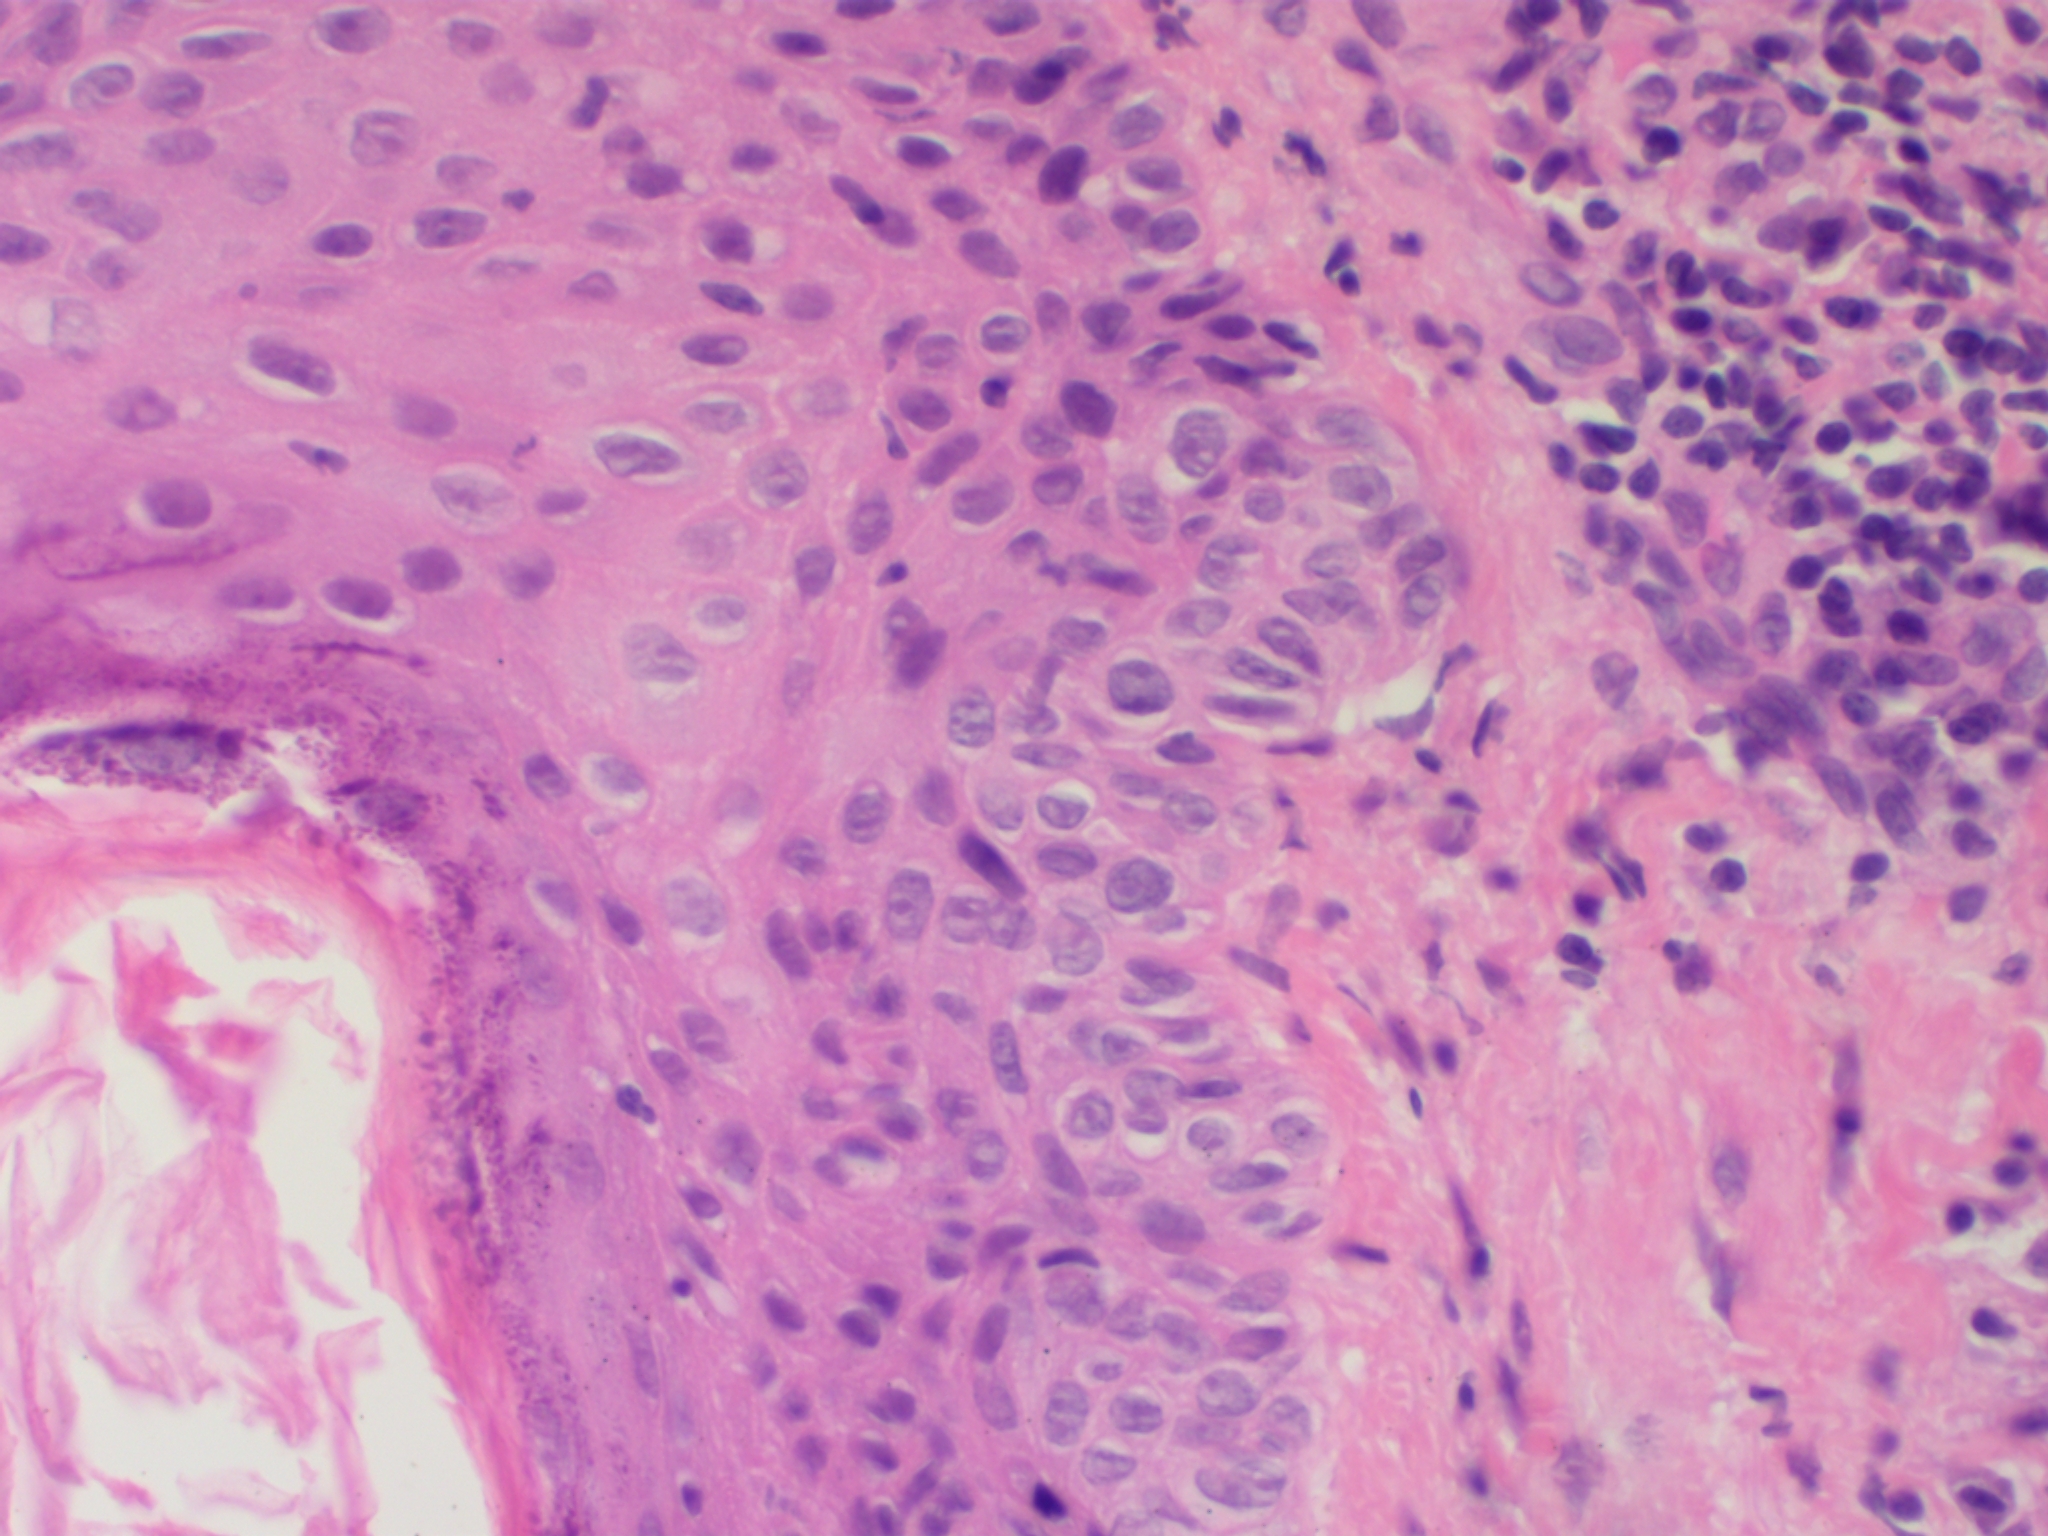

M. Paget is een traag groeiende tumor die uitgaat van apocriene klier afvoergangen. Histopathologisch ziet men aanvankelijk slechts enkele Paget cellen in de klierbuizen en de epidermis: grote, bleke cellen met een grote kern en helder cytoplasma. Zij zijn met dode celbrugjes verbonden met de cellen van het stratum spinosum. In oude laesies vervangen ze grote delen van het epitheel van de klierbuizen en ook van de epidermis. Deze cellen zijn PAS positief en diastase-resistent (verkleuring veroorzaakt door neutrale muco-polysacchariden). In de cutis is een banale ontsteking te zien. Vanuit het klierweefsel vindt tenslotte infiltratieve groei plaats. Het typische van de Paget-cel tumor is dat de cellen niet verhoornen, geen reuscellen vormen en de basale laag niet doorgroeien zoals andere tumoren (waarvan men ze moet differentiëren, b.v. m. Bowen en maligne melanoom).

PA-Foto's: Sarahkayb - Wikimedia - Creative Commons License 4.0